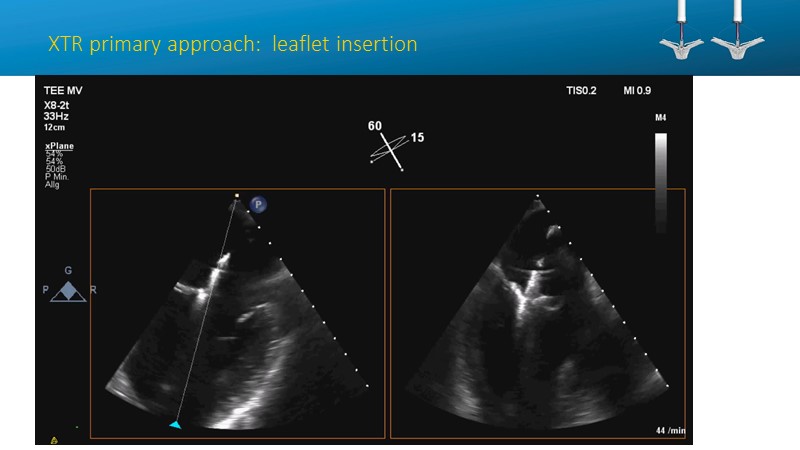

- To learn how will product innovation (Mitraclip NTR / XTR) drive improvement in procedural and clinical outcomes (EXPAND)